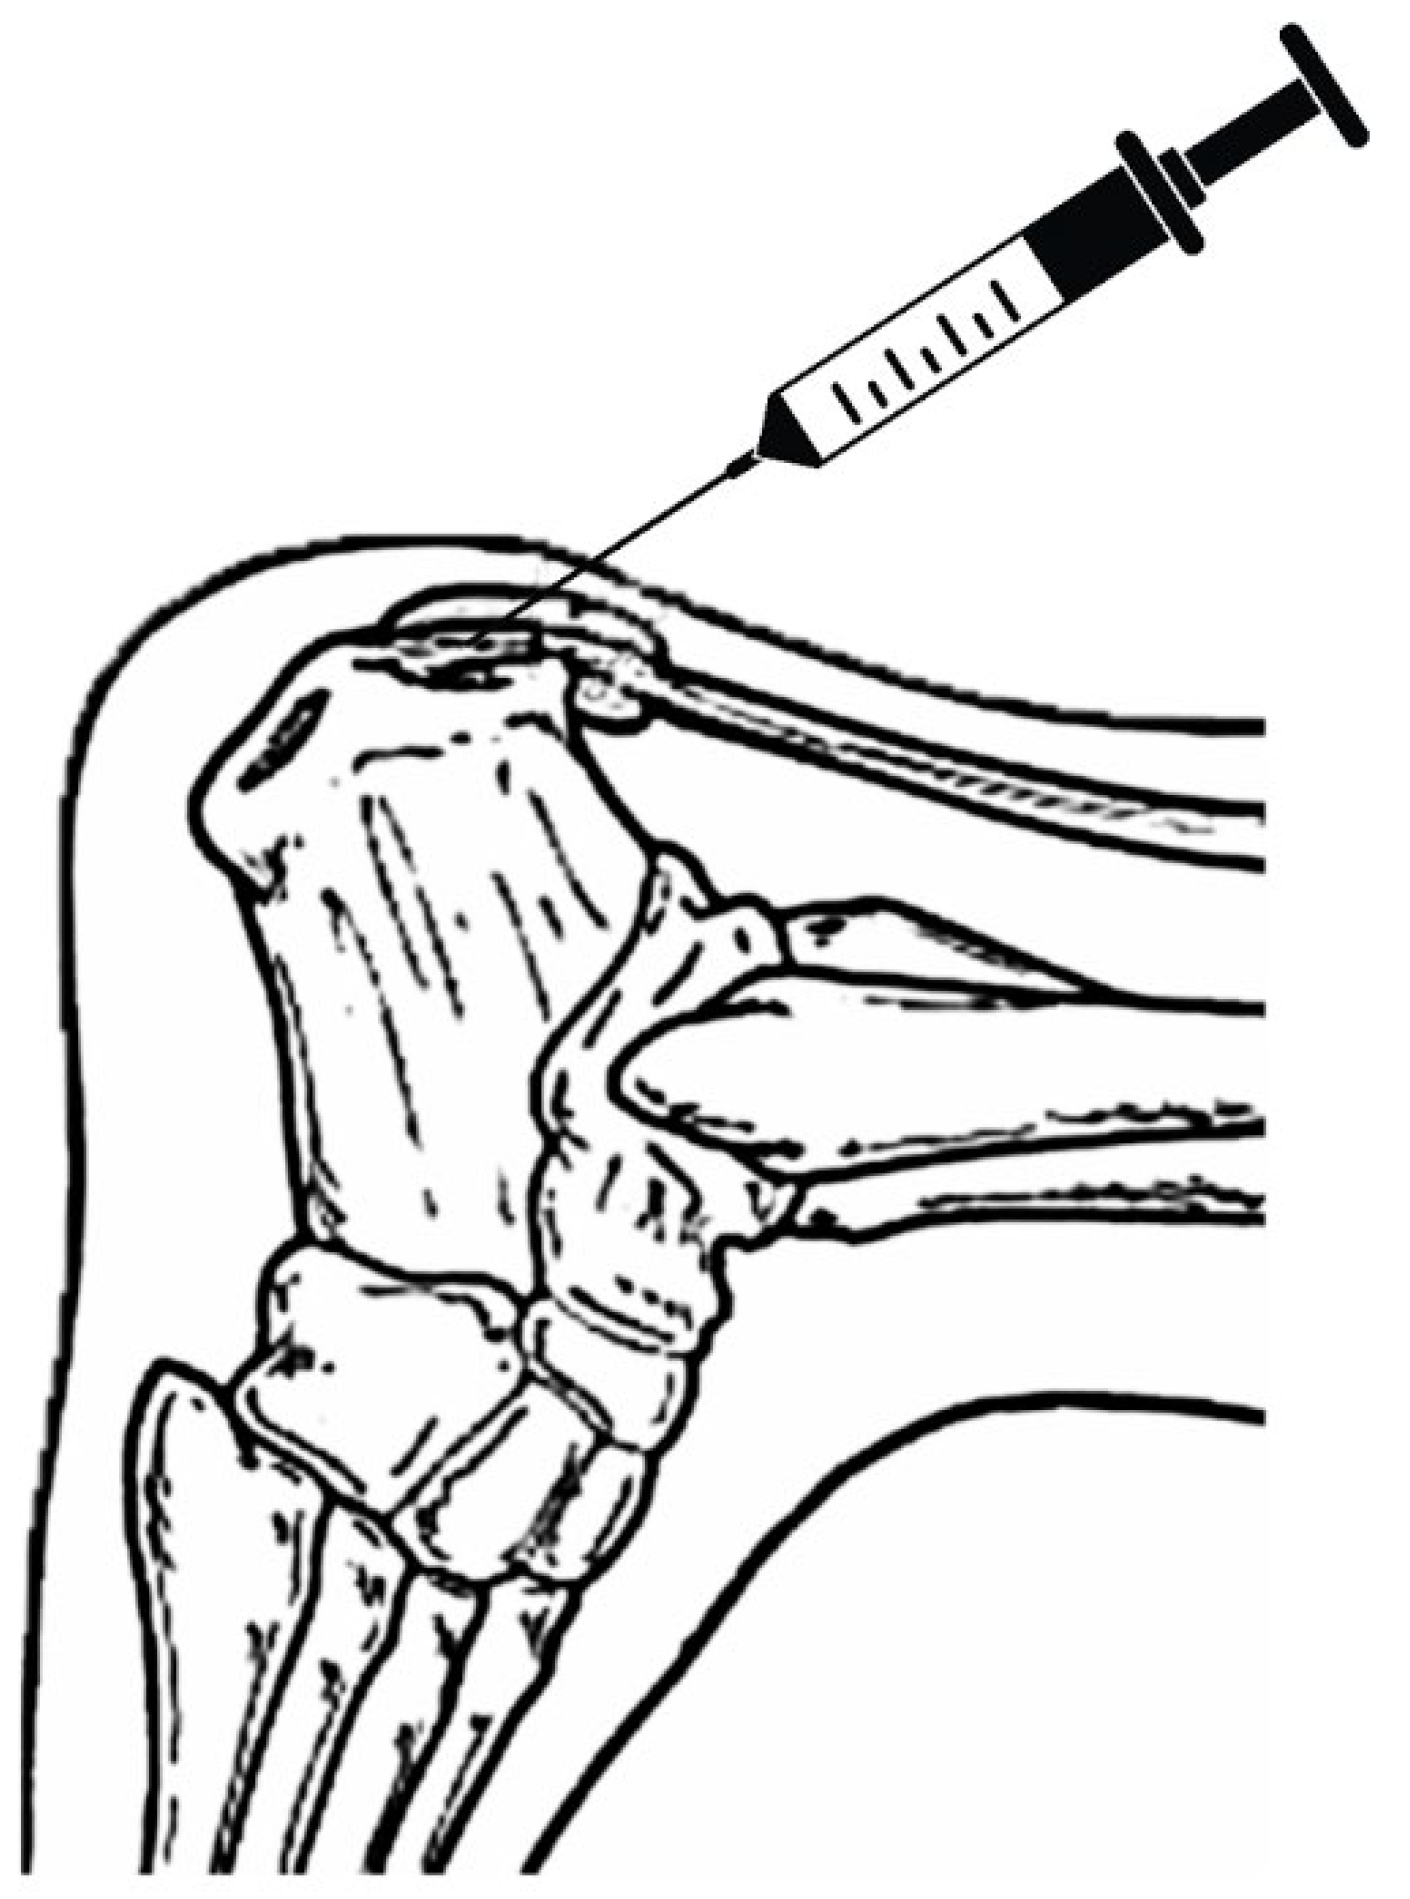

The procedure included the application of an umbilical cord tissue matrix, also known as Wharton’s Jelly, extracorporeal pulsed-activated therapy (EPAT), and class IV laser therapy. The patient was placed in the prone position without a tourniquet. It is essential to place the local anesthetic of choice more proximal away from the area to be treated. Lidocaine, 1% plain, was utilized to block the retrocalcaneal nerves, including the posterior tibial and sural nerves. The lower extremity was prepped and draped in the standard sterile technique. Prior to the application of the tissue allografts, the patient received EPAT at 11Hrtz, 1.4 bars, for 3521 pulses to the affected tissue. While the above EPAT was performed, 2ml of Cryotext, a minimally manipulated tissue allograft, was thawed slowly per laboratory guidelines in a 35-degree bath. Under real-time ultrasound guidance using Esoate My Labs 15.0 MHz with a 4cm transducer head (Figure 3, Figure 4 and Figure 5), the Wharton’s jelly allograft was transplanted along the insertion (enthesis) in the frontal plane in a fanning-like technique as well as fanning in the sagittal plane. This application was accomplished just proximal within the intratendinous area beneath the paratenon around the tendon proper by strategic supplementation, as well. Further “needling” with a 22 gauge needle was performed to encourage neovascularization. The patient was instructed not to take NSAIDs or steroids and to refrain from high-impact activities. The patient was scheduled for biweekly class IV laser treatments for the next three weeks to provide photobiomodulation, which has been shown to lower inflammatory markers [12]. A pneumatic boot was fitted for two weeks.